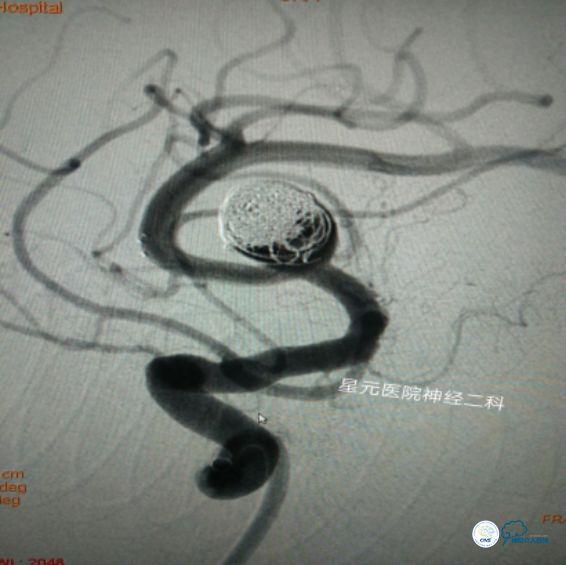

DSA回报:右侧大脑中动脉分叉处可见一14mm×11mm椭圆形动脉瘤,载瘤动脉为大脑中动脉M2段主干,其眶额支直接发自瘤体底部。左侧大脑中动脉分叉处可见一5mm×4mm球形动脉瘤。

方案一:冰激凌技术(支架托举弹簧圈)

➤用260泥鳅导丝将6F-115 Naviven,通过 8F GUIDING,在路图下缓慢送至颈内动脉海绵窦段,再将Headway17(标记为A)微导管,在0.014 微导丝的引导下通过Naviven超选入动脉瘤体内进行预留。重复上述步骤将另外一根Headway17(标记为B)微导管也超选入并预留到动脉瘤内。根据测量选择Solitaire颅内支架系统引入微导管(A),将支架输送致动脉瘤体中部精准半释放。

➤选用MicroVention 8mm—30cm弹簧圈,通过Headway17(B)缓慢进行瘤体栓塞,反复尝试后发现无法实现预计的弹簧圈托举,弹簧圈总是向瘤体底部盘旋(栓堵住了瘤体底部所发出的侧枝),且有缠绕支架的风险,随之放弃该方案。